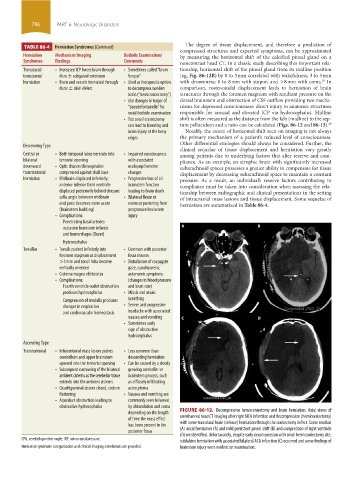

depending on the length FIGURE 86-12. Decompressive hemicraniectomy and brain herniation. Axial views of

of time the mass effect unenhanced head CT imaging after right MCA infarction and decompression (hemicraniectomy)

has been present in the with some transdural brain (release) herniation through the craniectomy defect. Some residual

posterior fossa (A) uncal herniation (A) and mild persistent pineal shift (B) and compression of right ventricle

(D) are identified. Unfortunately, despite early decompression with small hemicraniectomy site,

CPA, cerebellopontine angle; ICP, intracranial pressure. subfalcine herniation with associated bilateral ACA infarction (C) occurred and some findings of

Herniation syndrome categorization and clinical-imaging correlations are provided. brainstem injury were evident on examination.